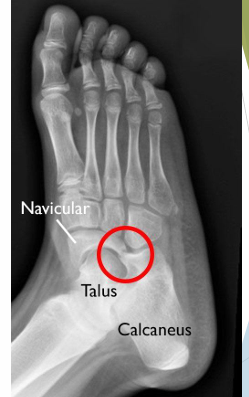

À quoi ressemble la coalition osseuse entre le 1 et 2 métatarse et naviculo-cuboidienne?

A